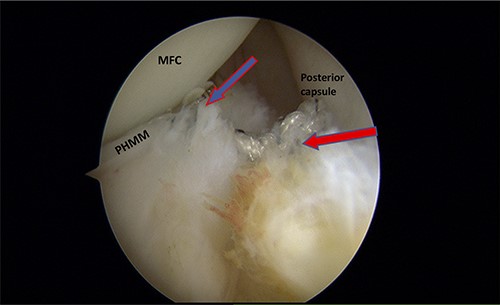

A posteromedial portal was utilized to repair both ramp tears using all-inside sutures, and curved suture hooks were inserted through the posteromedial portal. The first tear was repaired, and a non-absorbable suture was passed between the peripheral edge of the PHMM and attachment of the meniscotibial ligament (Fig. 6). The second tear was then repaired by passing the suture through the posterior capsular tissue, creating a bridge between the two tears to restore the meniscocapsular attachment (Fig. 7).

Trans-notch view of the postromedial compartment of the left knee showing the repair of both ramp lesion tears. The blue arrow indicates the repair of the first lesion at the meniscosynovial junction of the red-red zone area. The red arrow indicates the repaired second tear at the meniscocapsular attachment. PHMM, posterior horn of medial meniscus; MFC, medial femoral condyle